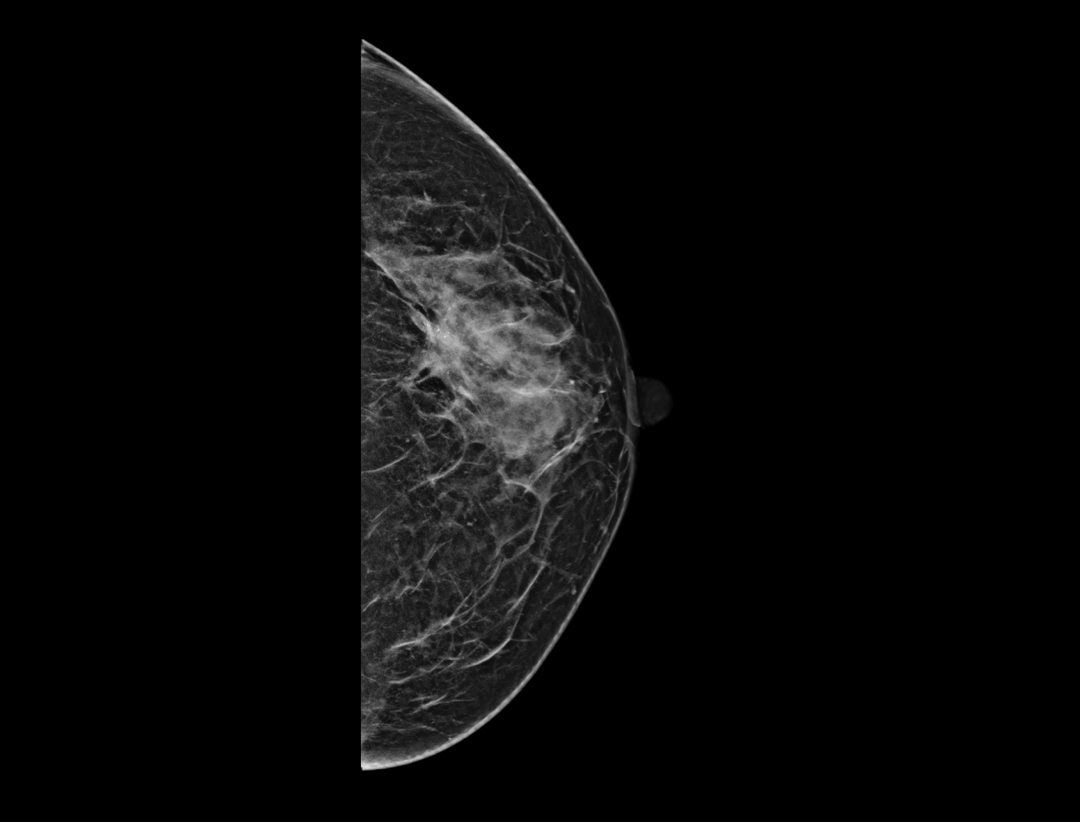

自定义层厚融合

更精细观察肿块及钙化簇的空间分布。